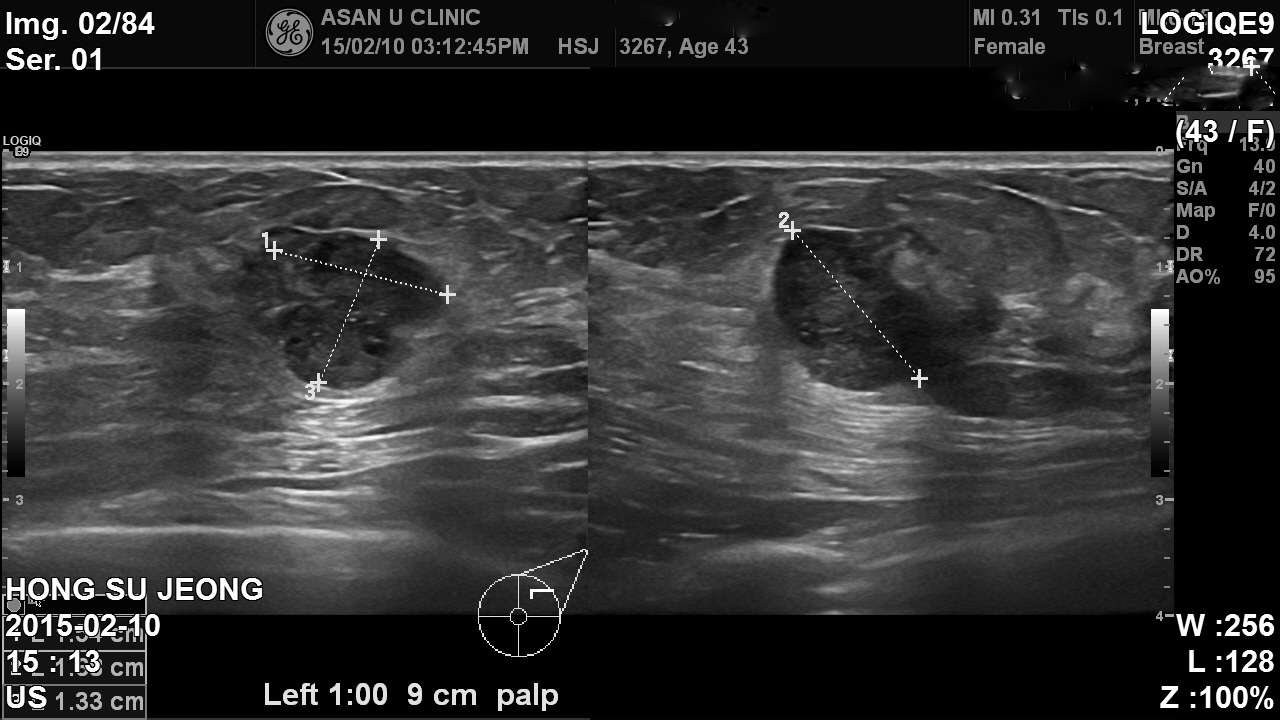

본원에 내원하신 40대 환자분이십니다.

유방초음파 후 좌측유방에1.92cm의 혹 조직검사시행하였고

침윤성유관암 진단되었습니다.